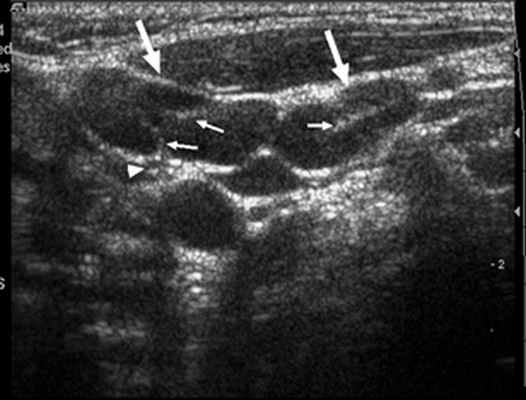

Поскольку визуальный осмотр позволяет произвести пальпацию лишь поверхностных лимфатических узлов, то для точного диагностирования, определения размеров, характера кровотока, а также вовлечение окружающих тканей, доктор предложит больному сдать лабораторные анализы, сделать УЗИ лимфатических узлов, МРТ (либо КТ) брюшной полости, либо грудной клетки. При необходимости назначают дополнительные исследования (например, биопсию лимфоузла).

Діагностичне обстеження передбачає використання інструментальних методів — УЗД. За його допомогою можна визначити форму й розміри лімфатичних вузлів, їхній зв’язок із навколишніми тканинами, наявність абсцесу. У разі потреби застосовують комп’ютерну чи магнітно-резонансну томографію, рентгеноконтрастну лімфографію.